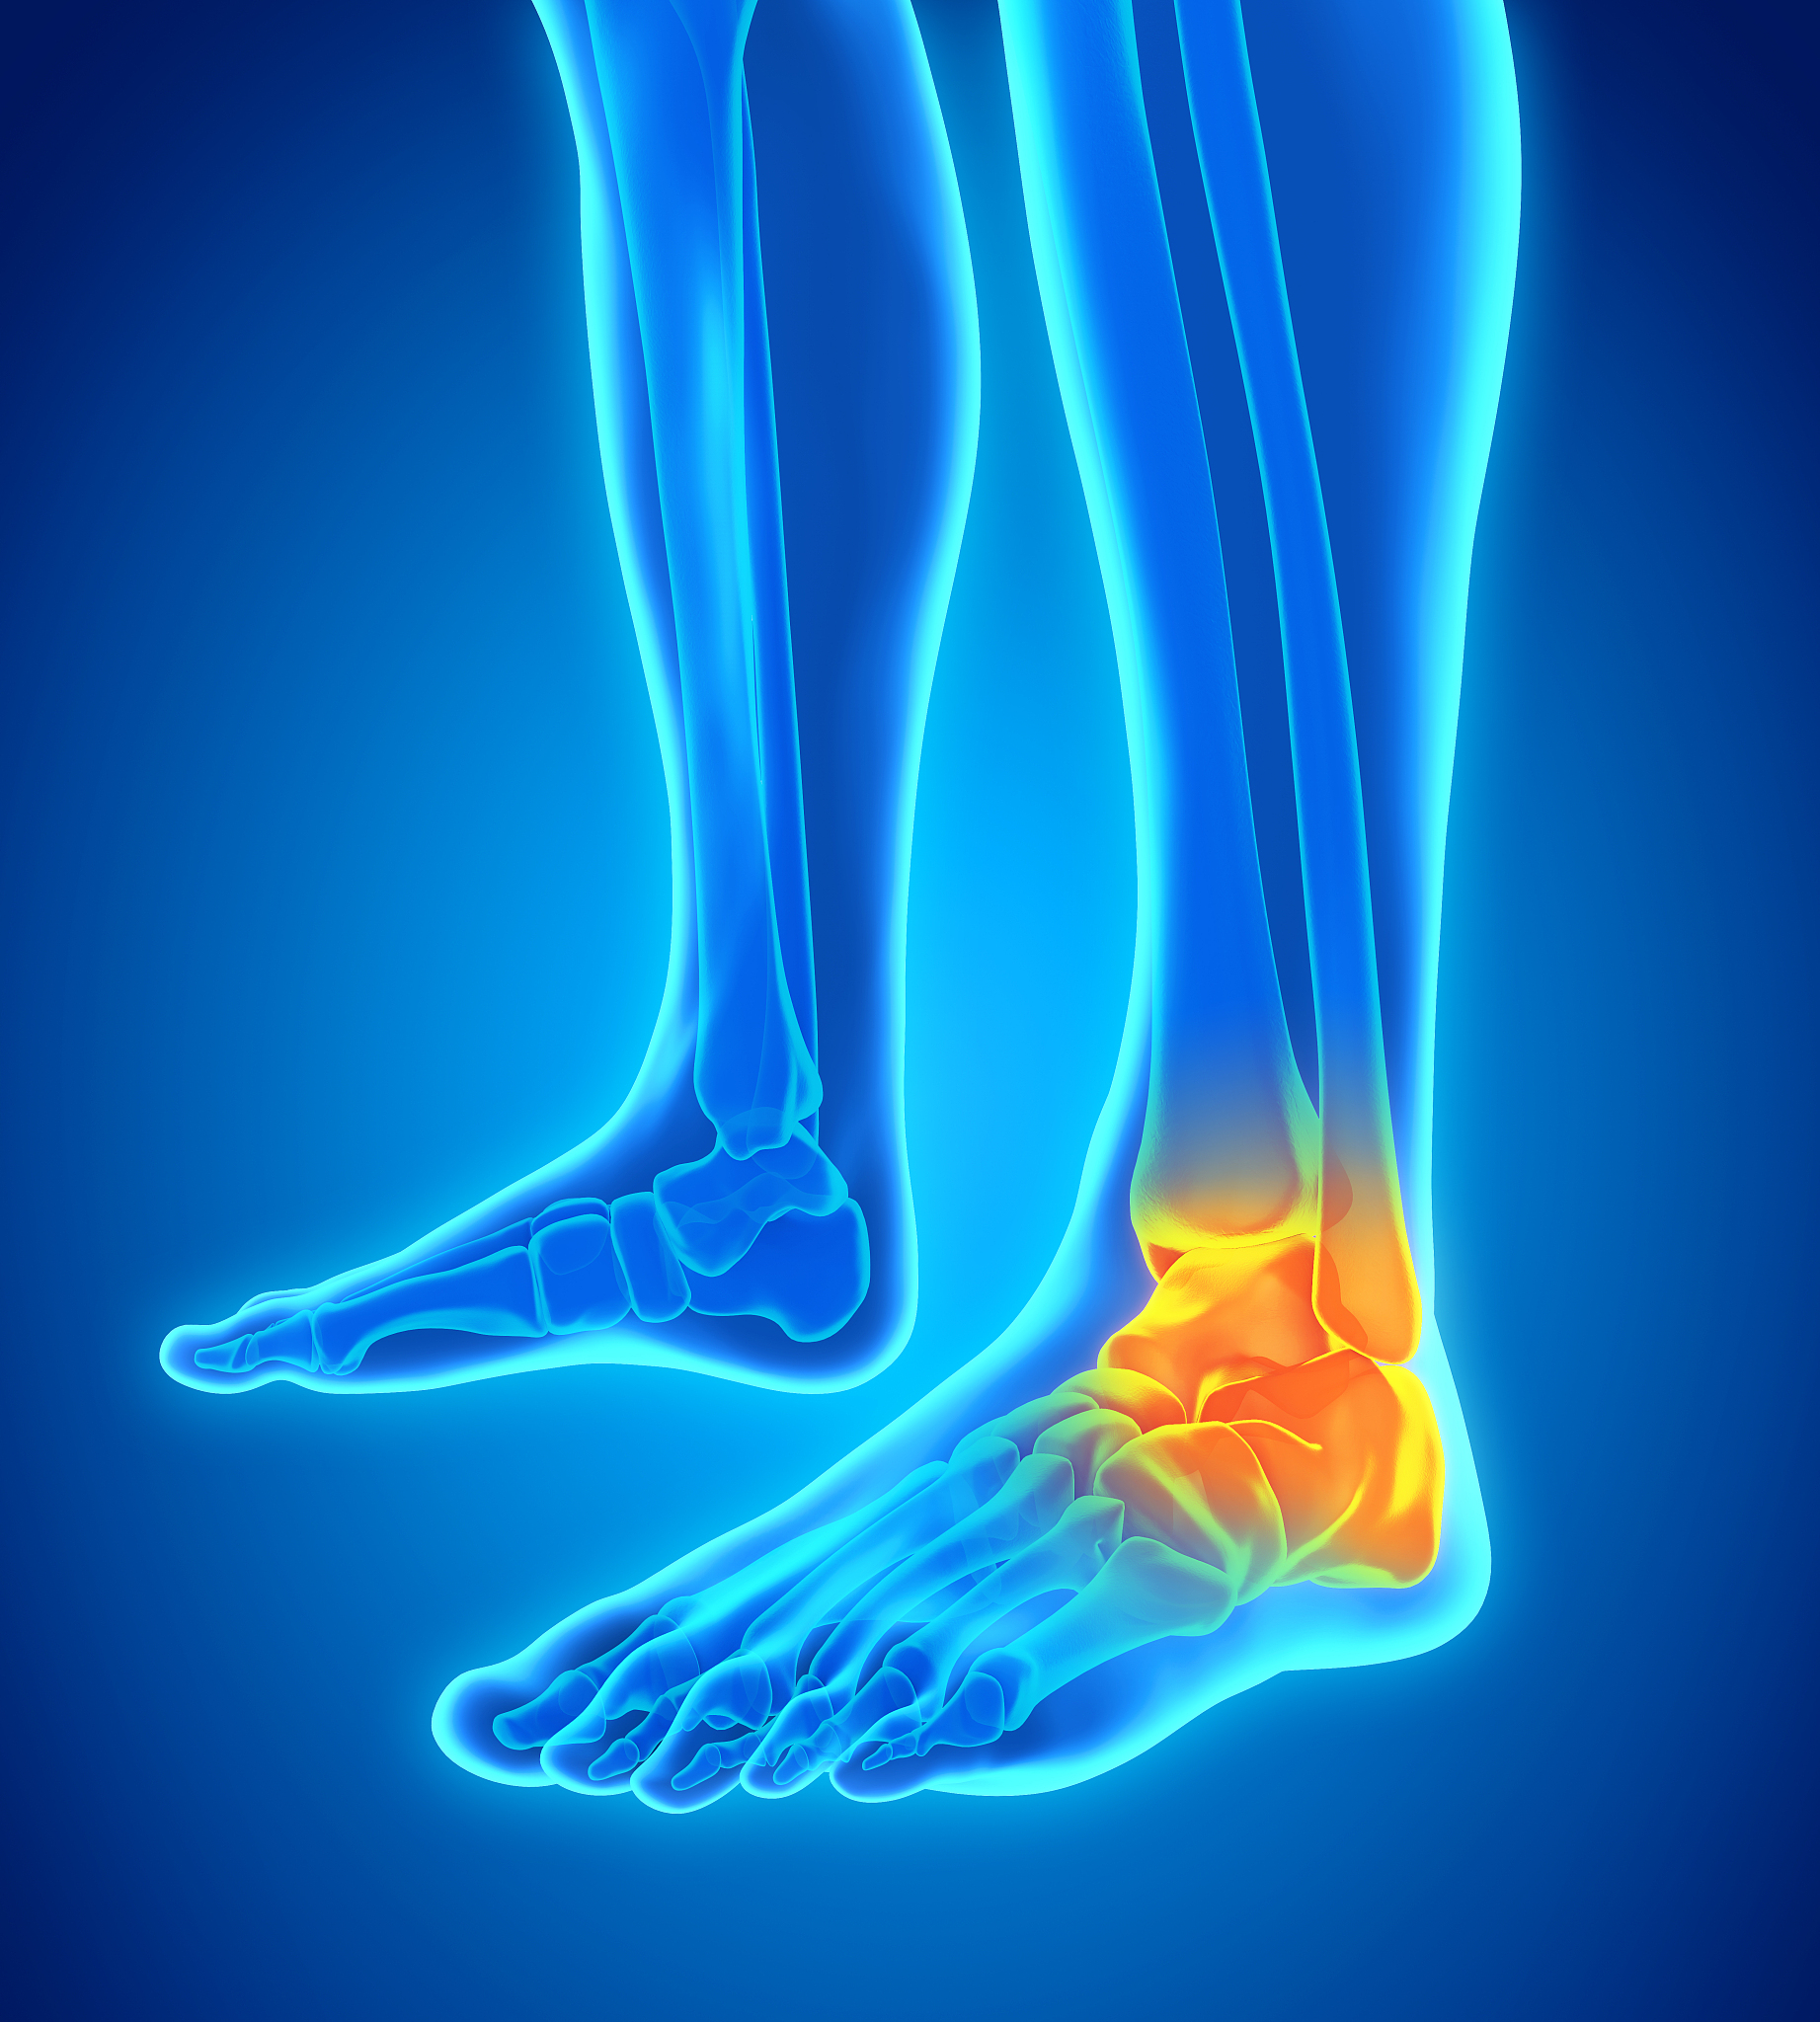

脚踝多次扭伤每次脚踝向内旋转时距骨处便会发生脆响这种情况可以恢复吗

如果脚踝多次扭伤导致距骨处发生脆响,可能表示距骨已经发生了损伤。建议您尽快就医,进行相关检查和治疗,以避免进一步损伤和加重症状。治疗可能包括物理疗法、药物治疗、手术等。同时,在康复期间也应该避免剧烈运动和重复受伤,加强脚踝的肌肉力量和稳定性,以防止再次扭伤。